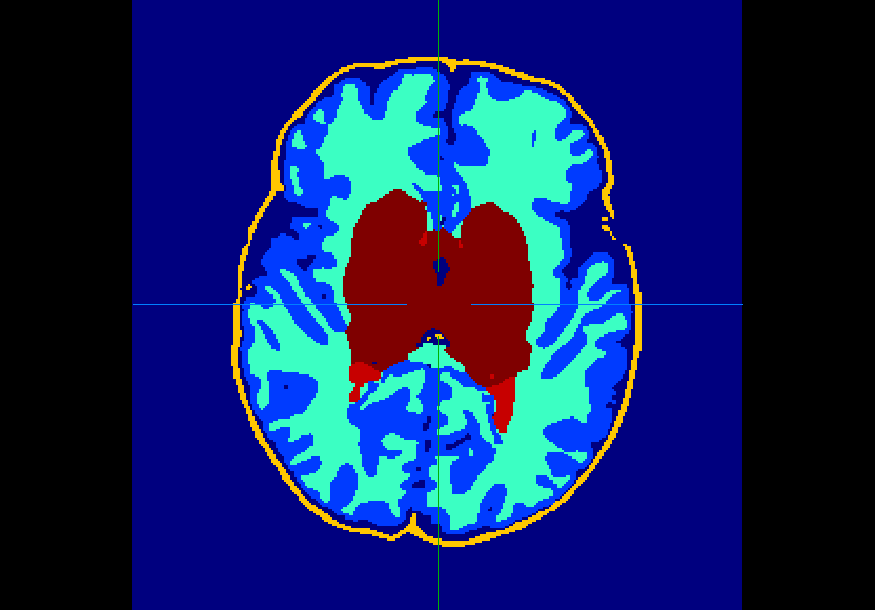

The dataset consisted of 70 3D T2-weighted brain MRI scans publicly available from the dHCP neonatal cohort. The segmentation maps had 10 classes, corresponding to: zero-pixel background, cerebrospinal fluid (CSF), cortical grey matter (cGM), white matter (WM), background bordering brain tissues, ventricles, cerebellum, deep grey matter (dGM), brainstem, and hippocampus. The scans covered an age range of 24.3-42.2 weeks. The data was available in NIfTI format; Figure 1 shows an example scan and corresponding tissue labels. We carried out a pre-processing step where each scan was independently normalised to zero-mean and unit-variance.